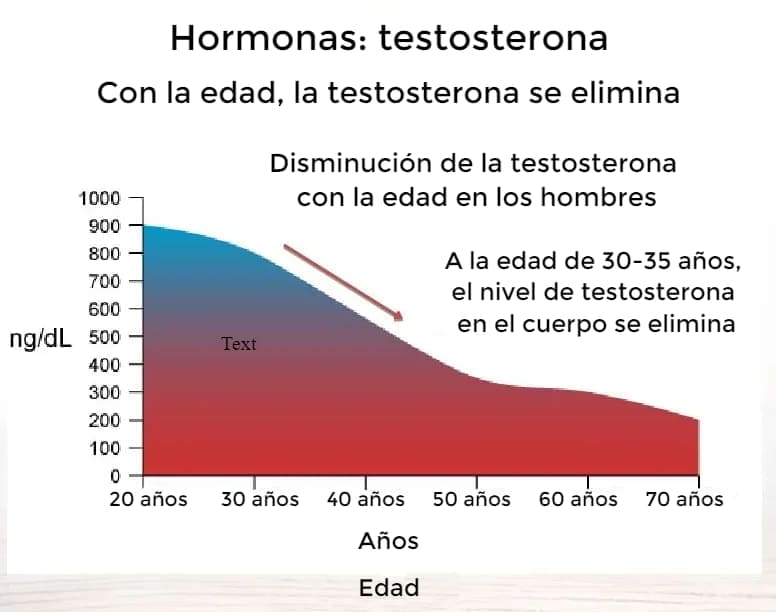

- Hay muchas razones. Pero lo más importante es una fuerte disminución en los niveles de testosterona. La disminución de los niveles de testosterona conduce a una disminución de la actividad sexual y, como resultado, al adenoma de próstata y la muerte por ello en el 90% de los casos.